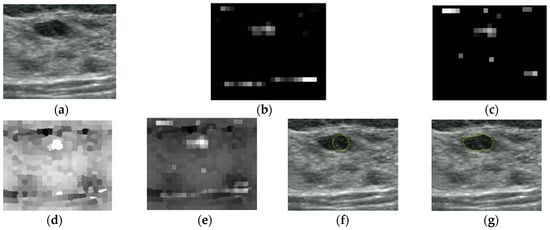

An Automatic Localization Algorithm for Ultrasound Breast Tumors Based on Human Visual Mechanism

Xie, Y.; Chen, K.; Lin, J. An Automatic Localization Algorithm for Ultrasound Breast Tumors Based on Human Visual Mechanism. Sensors 2017, 17, 1101. https://doi.org/10.3390/s17051101